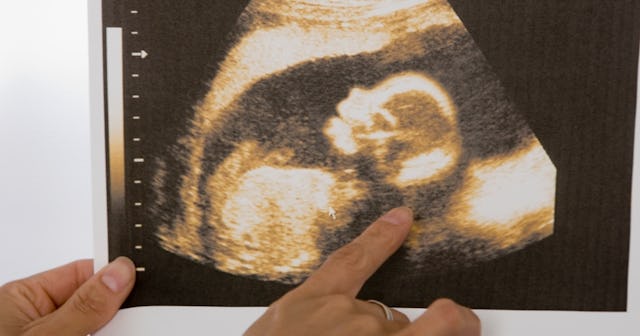

The Ramzi method, or Ramzi theory, was developed by Dr. Saam Ramzi Ismail and claims that you can predict a baby’s sex as early as six weeks into your pregnancy by determining how and where the placenta formed by viewing images from an ultrasound. According to the Ramzi method, if your placenta is forming on the right side of your uterus, the baby is most likely a boy. If it’s forming on the left side, it’s probably a girl.